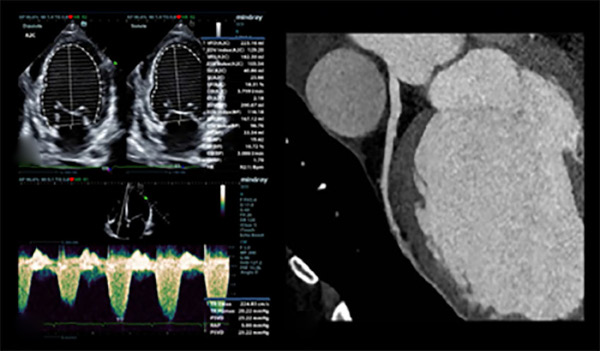

Figura 1

Ecocardiograma Doppler color realizado durante la internación donde se evidencia FEVI 29% (A) y jet de insuficiencia tricuspídea leve (B); angiotomografía coronaria, con arteria descendente anterior sin lesiones (C).

Posteriormente consulta nuevamente por guardia externa en dos oportunidades por presentar edemas en miembros inferiores, por lo cual se decide su internación para diagnóstico y control. Se hace diagnóstico clínico de insuficiencia cardiaca aguda. Se solicita ecocardiografía transtorácica, que evidencia de miocardiopatía dilatada con deterioro grave de la función ventricular, fracción de eyección ventricular izquierda (FEVI) 29 %, con hipocinesia global debido a lo cual se decide su internación en Unidad Coronaria (UCO) para estudio y tratamiento. Durante la internación se logra recabar antecedente familiar y diagnóstico genético y biopsia muscular (realizados a los seis años de edad) de distrofia muscular de Duchenne (DMD), que ha tenido seguimiento irregular y sin tratamiento médico.

En UCO se indica balance hídrico negativo; pulso de levosimendan; y se inicia tratamiento médico completo para insuficiencia cardíaca avanzada. Durante la internación se realiza ecocardiograma con medición de strain (- 14 %); angiotomografía computada coronaria con score de calcio donde no se evidencian lesiones; resonancia magnética nuclear (RMN) cardíaca con gadolinio que constata miocardiopatía dilatada con patrón de realce tardío mesocárdico que involucra el sitio de unión entre miocardio ventricular derecho e izquierdo y anteroseptal e inferoseptal, además de realce subepicárdico anterolateral e inferolateral, patrón que también se encuentra descrito en otras entidades como la miocardiopatía dilatada idiopática y la miocarditis. Además se solicita ECG Holter de 24 hs que solo evidencia extrasistolia supraventricular de baja densidad. Luego de seis días de internación, se otorga el alta sanatorial con indicación de derivación a centro de trasplante de forma ambulatoria.